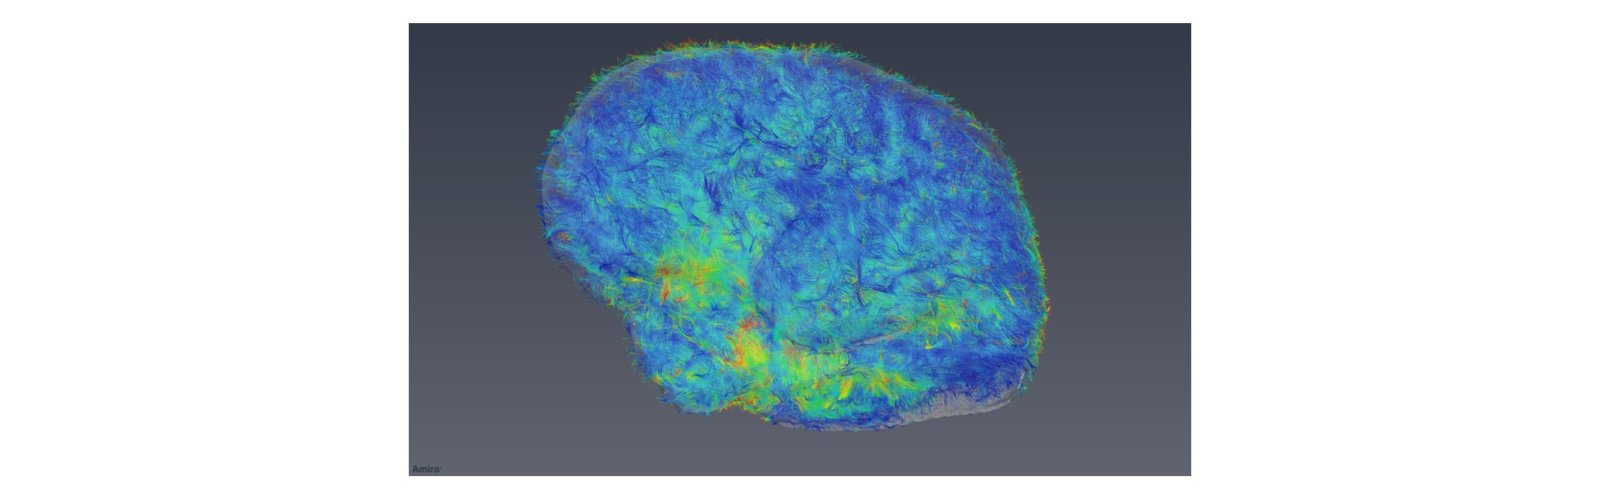

To provide image processing and analysis service to help scientists and clinicians develop imaging biomarkers using different imaging modalities with the goal of:

• Detecting and diagnosing diseases to enable an early stage to enable early treatment intervention.

• Tracking disease progression/tissue regeneration allowing clinicians to evaluate the medical condition.

• Monitoring treatment effects either via conduits for drug delivery and regenerative medicine applications or via other interventional procedures to facilitate therapeutic mechanisms.